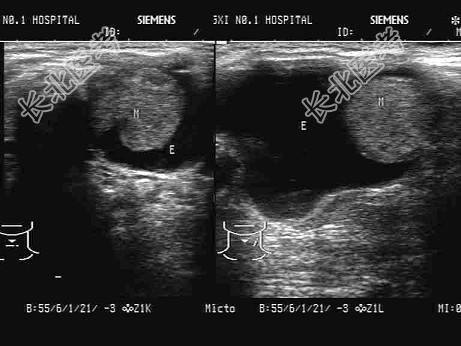

- 单项选择题患者,女, 66岁,近半月颈部明显增大。超声检查如图, 以下最可能的诊断为 ( )

A、甲状腺炎

B、甲状腺乳头状囊腺癌

C、甲状腺囊肿

D、甲状腺腺瘤并囊变

E、结节性甲状腺肿